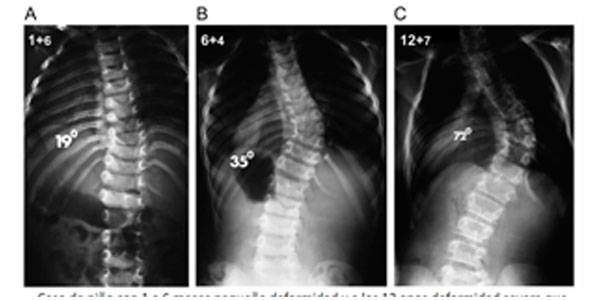

Paciente de 1 año y 8 meses con escoliosis congénita progresiva, se realizó resección de hemivertebra con colocación de tornillos transpediculares

Se necesitará controles periódicos (4-6 meses) para comparar con estudios radiográficos si la curva está aumentando o está detenida.

El 75 % tienden a progresar, con frecuencia la cirugía precoz permite que el paciente evite una cirugía mucho más extensa más adelante.